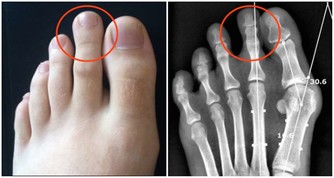

供應部位:生殖器官、子宮、膀胱、膝;神經受壓後果:膀胱病、月經不調、小產、膝痛

供應部位:小腿、踝、腳;神經受壓後果:腿部血液循環不良、腿無力、足踝腫痛